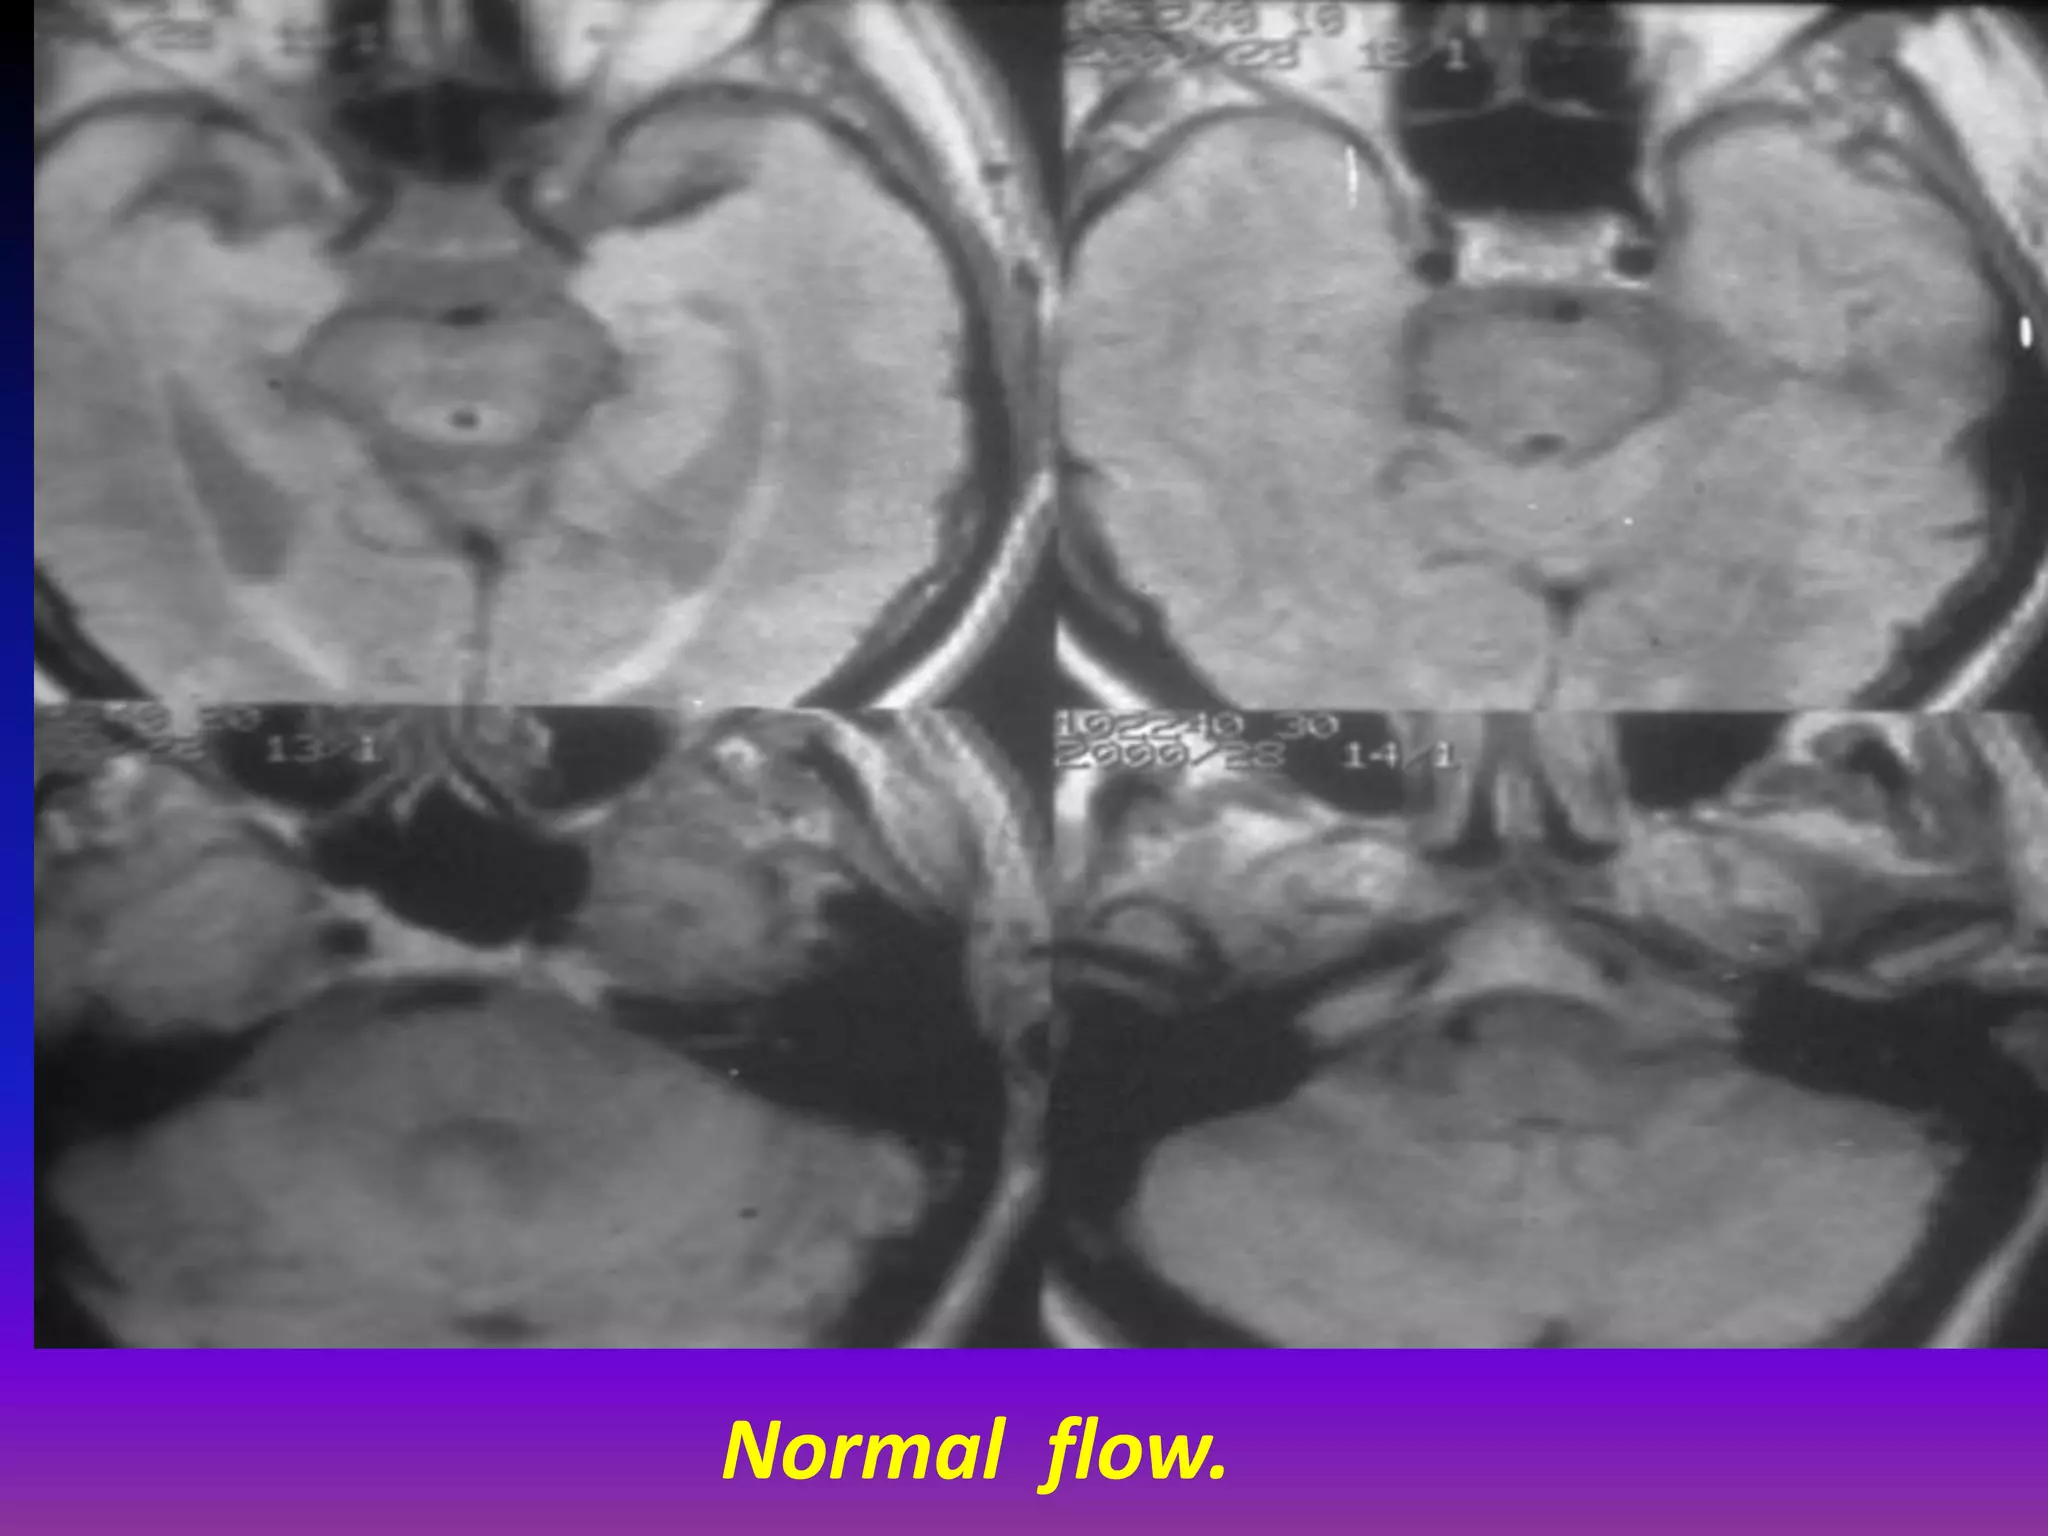

Normal flow.